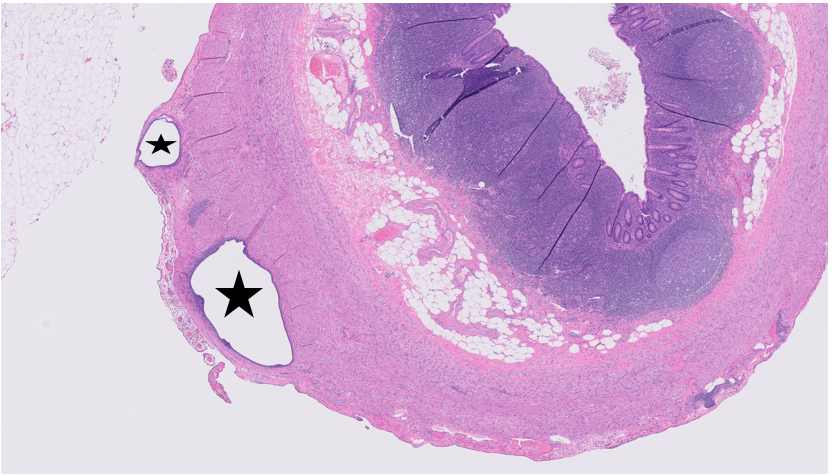

Fig. 4 Histopathological examination showed endometrial glands in the middle of muscle layer of sigmoid colon (×100) (Stars pointed)

Fig. 5 Histopathological examination showed endometrial gland in the middle of muscle layer of sigmoid colon in diffrent slides (×100) (arroows pointed)

The diagnosis was confirmed with histopathology (Fig. 4-5), showing endometrial glands within the muscular layer of the sigmoid colon. Postoperatively, the patient made a full recovery, reporting no further abdominal symptoms. Ongoing postoperative management of endometriosis includes hormonal therapy with an IUD which was placed in 2023. The patient continues follow-up visits with her OB-GYN for further care and symptom control.